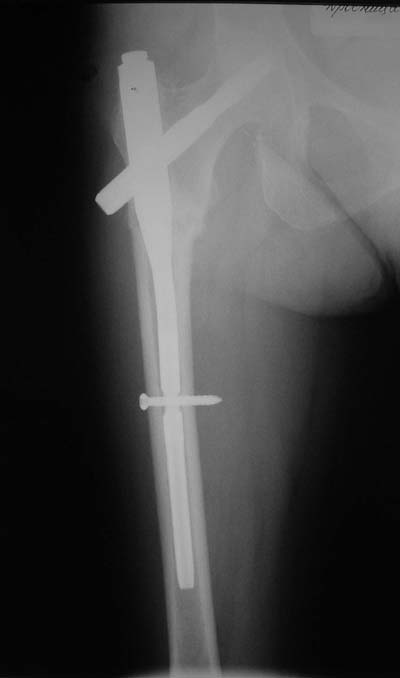

Да? Качество рентгенограмм конечно неочень, но ведь это нестабильный перелом 31.А2.2, не так ли?

Не думаю так. см вложение.

> Да? Качество рентгенограмм конечно неочень, но ведь это

Ну, после помещения туда такого гвоздя даже без дистального винта заметной нестабильности уже не остается ;-)